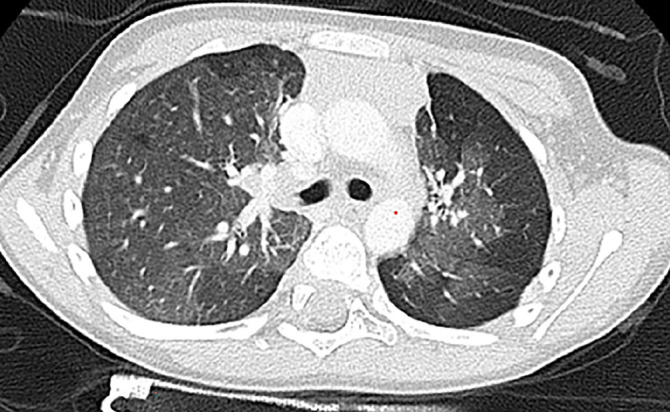

Results: Sixteen patients were enrolled. Median age at diagnosis was 27.5 months (range: 7-195 months). Wheezing was the most common presenting symptom. The most prevalent finding on thoracic CT was a mosaic pattern. In all but one, a wide range of variations genes related to both pulmonary structure and function were identified. The genes identified included those related to primary ciliary dyskinesia (DNAH genes), surfactant metabolism disorder (ABCA3, CSF2RB), pulmonary fibrosis (MUC5B, SFTP), and bronchiectasis (SCNN1B).